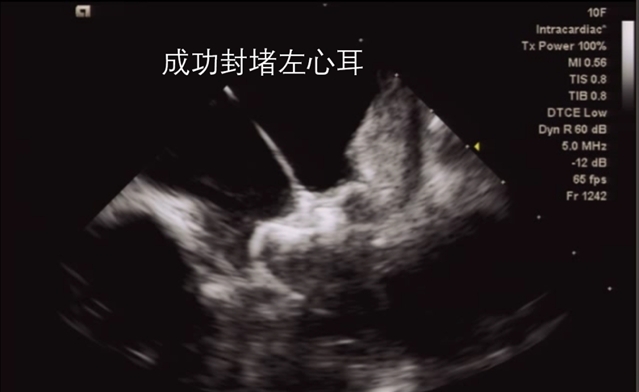

七、2021.05.14我院第一台在心腔内超声指导下的左心耳封堵术:

此次手术为我院首台心腔内彩超(ICE)指导下的左心耳封堵术,也是我市少有的基于ICE建模,局麻下完成的封堵术。术者为我院心内科陈弹主任医师。其意义不仅在于为房颤患者提供新的预防卒中的策略,还标志着我院心血管内科团队在心脏介入诊疗领域迈上了新台阶。